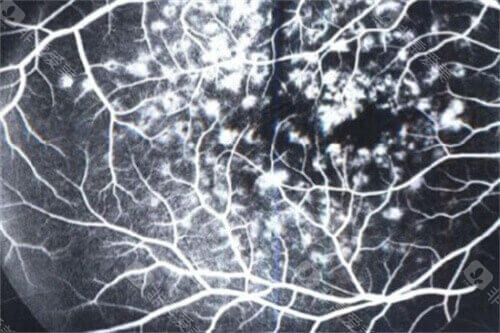

医院眼底病专科设备可靠,拥有国内外很棒的眼科检查及手术设备,包括光学相干断层扫描仪(OCT)、眼底荧光造影仪、视觉电生理检查仪、超声生物显微镜(UBM)等。

医院黄斑疾病中心是西北地区较早成立的黄斑病专病诊疗中心,拥有一支技术优质的医疗团队。

中心开展各种黄斑疾病的诊断和治疗,包括老年性黄斑变性、黄斑水肿、黄斑裂孔、黄斑前膜等,年手术量超过1000例。